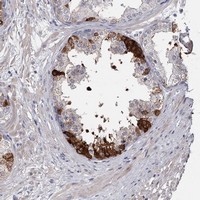

- Immunohistochemical staining of human prostate with FDXACB1 polyclonal antibody (Cat # PAB23380) shows strong cytoplasmic positivity in glandular cells at 1:50-1:200 dilution.

- Immunohistochemistry (Formalin/PFA-fixed paraffin-embedded sections)